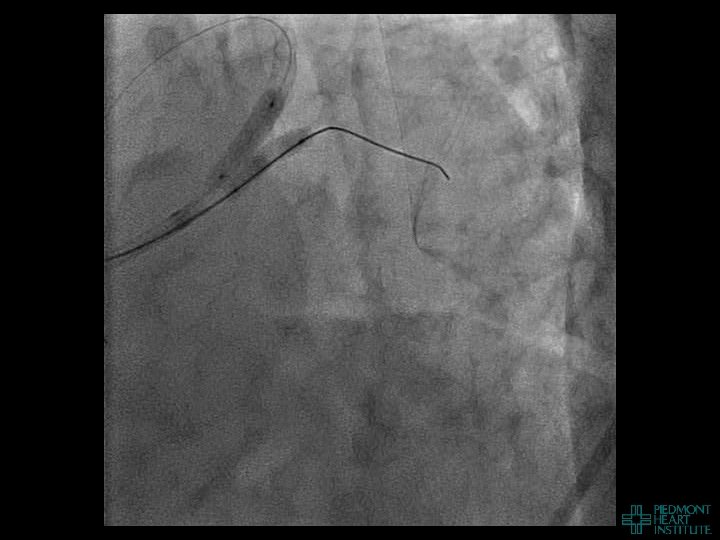

Coronary Perforation Methods of Patient Management • Dual Catheter (‘Ping Pong’) Technique • Prolonged

Coronary Perforation Methods of Patient Management • Dual Catheter (‘Ping Pong’) Technique • Prolonged balloon inflation and covered stents • Reversal of anticoagulation — Know contradictions to protamine sulfate for UFH; Avoid bivalirudin, LMWH — Reserve GP 2 b 3 a inhibition until successful crossing and wire change-out Embolization • — Coil, gelfoam, methacrylate, autologous blood/fat • Microcatheter Occlusion • Confirmation of successful management — Contralateral injection — Right heart catheterization — Echocardiogram — Contrast echocardiography